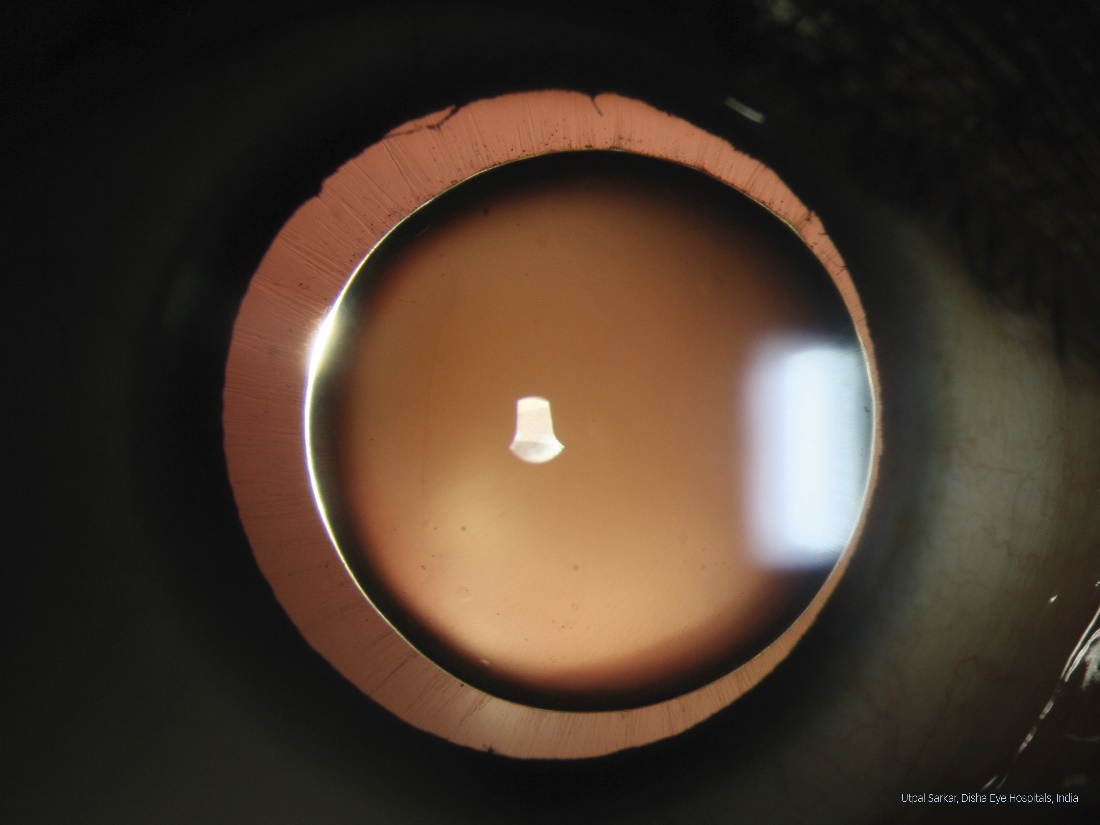

First place has been awarded to Utpal Sarkar from Disha Eye Hospitals Barrackpore in Kolkata, India. His winning image, taken with a Haag-Streit BX 900 slit lamp imaging system, shows a case of Spherophakia and convinced on all three winning criteria, i.e., image quality, technical execution, and disease interest. The jury was especially impressed by the ciliary zonule being fully in focus over nearly the entire 360 degrees of the eye. In addition to receiving the highly coveted ‘Slit Lamp Imaging Competition 2022’ trophy, Mr. Sarkar will also be featured in an ophthalmic journal and will receive a Sony Alpha 7 IV Kit as 1st prize.

1st place: The winning picture by Utpal Sarkar from Disha Eye Hospitals Barrackpore showing a patient with Spherophakia